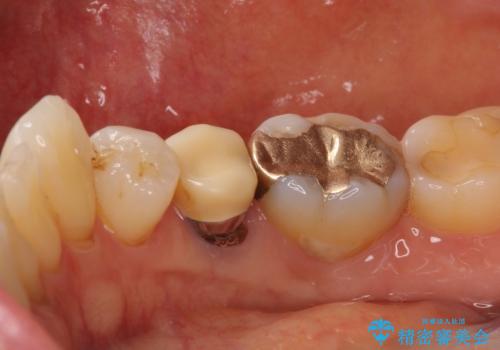

歯に穴があいた 奥歯のセラミック治療

- メインテナンスの際、以前よりものが挟まることが気になっていた患者様です。

神経が取り除かれた歯であるため、虫歯で歯が失われていく際に痛みを伴わなず、気がついたら大きな穴があいていました。

虫歯を全て除去したうえで新しい土台を築製し、セラミッククラウンにより補綴治療を行うこととしました。